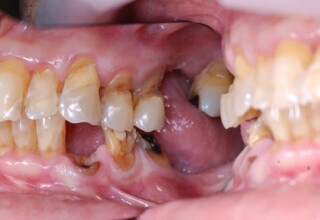

Lower jaw: extractions, direct implant placement and immediate loading (same day) with a transitional bridge.

Upper jaw: Sequential extractions, sequential implant placement and gradual incorporation in the temporary bridge so that the patient was never left without fixed teeth. The aim of the above approach was to have the patient in continuous functional and aesthetic reconstruction, without immediate loading due to anatomical restrictions. Old smiling photos of the patient were used because the natural shape of the teeth was completely lost due to repetitive prosthetic attempts. Tooth relationship and teeth-lip support was transferred to the temporary restorations. Two different transitional bridges were needed to fully estimate phonetics, mastication and esthetics. After the necessary adjustments were finalized, the temporary bridge was used as a guide for the permanent bridges.

Initial

Intermediate

Final